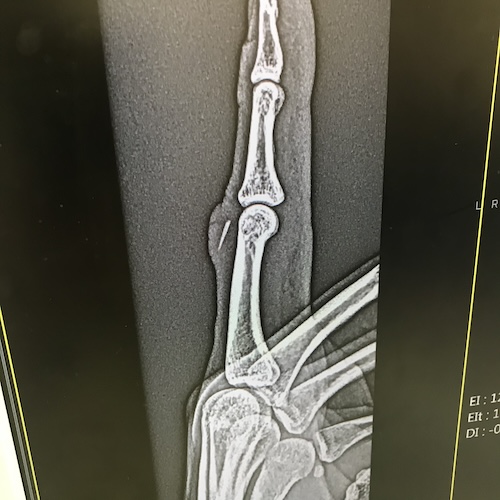

そしてそのような、意思決定の中にお客さんの顔が介在しないよこしまな仕入れを行ったためか、6年前くらいに右手の人差し指にこの魚の背鰭が刺さり埋没。「まあ大丈夫だろう」と半年ほど放置した結果ある日急に該当箇所がパンパンに腫れ上がり、慌てて病院に行ったところ、きちんと切開して除去しなければならない程度には厄介な状態になっていた。

あとその時した医者との「なんでほっといたの〜?痛かったでしょ〜」「なんかいずれ溶けてなくなるかな、と思って」「溶けないよ〜」のやり取りから「体内に入った異物は基本的に溶けて無くなったりしない」、加えて「腹腔内に残置されたメスがカルシウムの殻に覆われて奇跡的に他の臓器を傷つけず医療ミスがバレない、なんてことはない」も見出せるだろう。